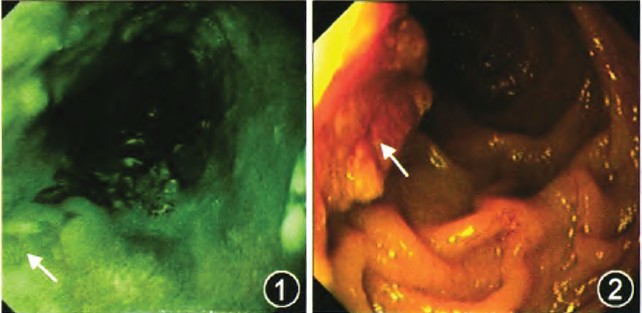

内镜及病理诊断为:十二指肠乳头癌,食管鳞癌(图1~4)。

图1 胃镜示食管局部黏膜呈边界不规则的片状隆起型糜烂,中央轻度凹陷,窄带成像(NBI)模式下病变区域呈褐色(箭头所示)

图2 胃镜示十二指肠乳头呈菜花状隆起(箭头所示),黏膜组织明显增粗、糜烂,组织较脆,易出血